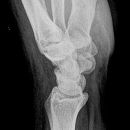

Handgelenk seitlich

Beurteilungskriterien

• Neigung der distalen Radiusgelenkfläche in der Sagittalebene: 10 – 15°

• Kontinuierliche Verlängerungsachse durch Radius, Lunatum, Capitatum und Os metacarpale III. Kontinuität von Handrücken und Unterarmrückfläche (Luxation, nicht-exakte Einstellung? -> Proc.styloideus ulnae im hinteren Radiusdrittel?)

• Scapholunärer Winkel 30 – 60°

• Verstreichen und Ventralverlagerung der volaren Fettstreifen vor dem M.flexor digitorum profundus und M.pronator quadratus

• Grundsätzlich gilt: unklare Verhältnisse -> CT-Indikation